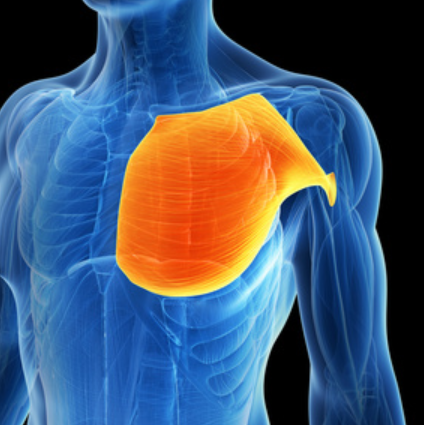

Treating Trigger Points - Pectoralis Major

Treating Trigger Point in Pectoralis Major - Dr. Jonathan Kuttner More About Shoulder Pain Pectoralis Major - Common Trigger Point Sites Notes The pectoralis major can...